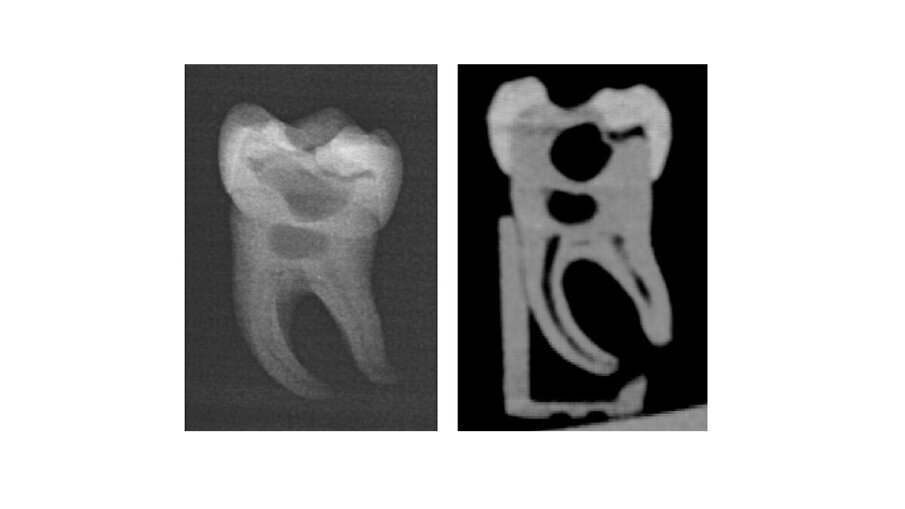

WÜRZBURG, Alemanha: Os avanços na tecnologia de impressão 3D têm o potencial de transformar a forma como os futuros dentistas aprendem habilidades práticas. Um novo estudo destacou o potencial de um modelo de molar impresso em 3D para aprimorar o treinamento endodôntico de estudantes de odontologia. Desenvolvido a partir de microtomografias computadorizadas de um dente humano extraído e fabricado com estereolitografia de alta resolução, o molar artificial replicou fielmente a anatomia complexa dos canais radiculares naturais e superou os blocos de acrílico convencionais, oferecendo uma ferramenta promissora para complementar e aprimorar os métodos tradicionais de treinamento.

No estudo, pesquisadores da Universidade de Würzburg desenvolveram um dente de treinamento impresso em 3D realista com anatomia natural do canal radicular e avaliaram sua eficácia integrando-o a um curso de formação para estudantes de odontologia. Os estudantes de odontologia, que já possuíam experiência com blocos de treinamento de acrílico e dentes extraídos, realizaram o preparo do canal radicular e a obturação no dente impresso utilizando sistemas rotatórios e reciprocantes. Em seguida, foram solicitados a preencher um questionário comparando o dente impresso com blocos de acrílico e dentes naturais em métricas como realismo, adequação, manuseio, sucesso no aprendizado e desejo de treinamento futuro.